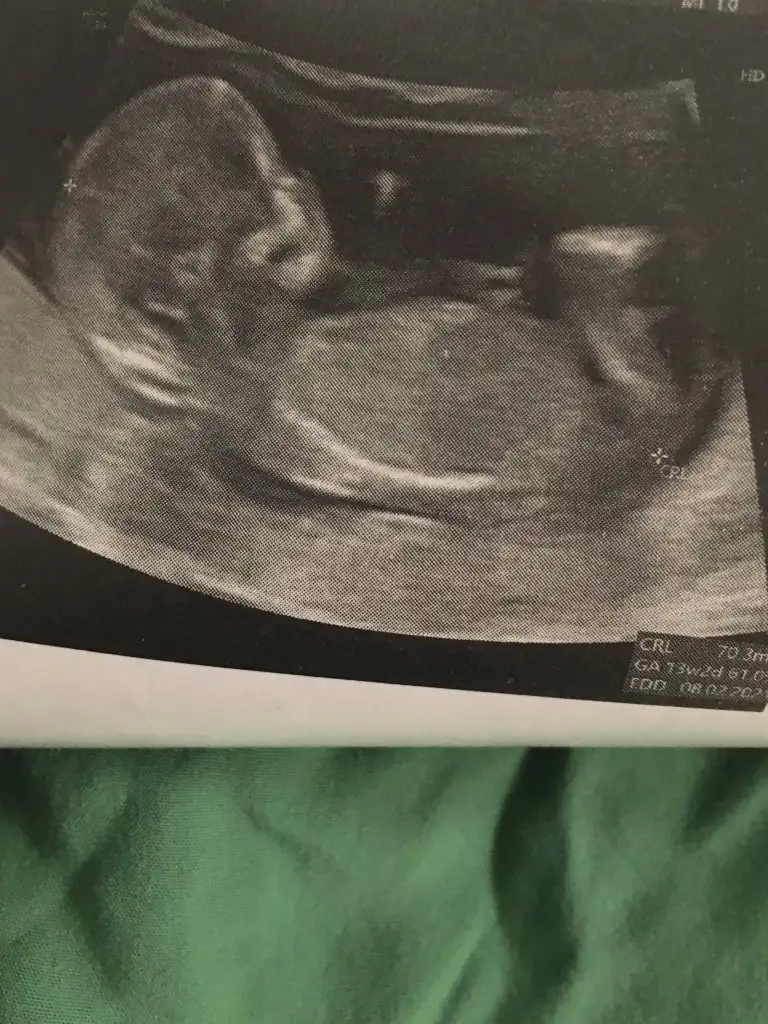

M mely15 bir bakarmisin tahminin nedirIkraammmm bugun girdim ultrasona dr 10+5 gunluk dedi belli oluyormu burda canim Eki Görüntüle 2676525 Eki Görüntüle 2676526 Eki Görüntüle 2676525

Gulum hamilelik iyi gidiyor hamd olsun 9hafta 4 gunluk ama doktor 10 hafta 5 gunluk gorunuyor dedi hatta iki tane ultrason kagidi verdi birinde 10 +5 digerinde 11 yaziyor nub falan gorunmuyormu kizlar

Yok nub göremedim net değil cnmGulum hamilelik iyi gidiyor hamd olsun 9hafta 4 gunluk ama doktor 10 hafta 5 gunluk gorunuyor dedi hatta iki tane ultrason kagidi verdi birinde 10 +5 digerinde 11 yaziyor nub falan gorunmuyormu kizlar

Ikram simdi gordum bu msjini ben bu isaretlediklerimi nub saniyorum kiz hala cozememisim desene nub degil bunlar galiba birde zaten birinde bana gore dik digerinde paralel sanki terzi misali kendi sokugumu dikemiyorum aklim erkekte ya her cikintiyi pipi saniyorum galibaSen daha iyi görüyorsun USG yi resim net değil sen ne diyorsunbebisine

Yok değil nub hiç belli değil canimIkram simdi gordum bu msjini ben bu isaretlediklerimi nub saniyorum kiz hala cozememisim desene nub degil bunlar galiba birde zaten birinde bana gore dik digerinde paralel sanki terzi misali kendi sokugumu dikemiyorum aklim erkekte ya her cikintiyi pipi saniyorum galiba

Anladim canim haftaya persembe ikili taramaya gonderdi ozelde yaptiriyorum o testleri ordaki usg daha iyi belki belli olur oradaki dr 12 haftada kizlari bilmisti yine buraya atarim haber ederim canimYok değil nub hiç belli değil canim